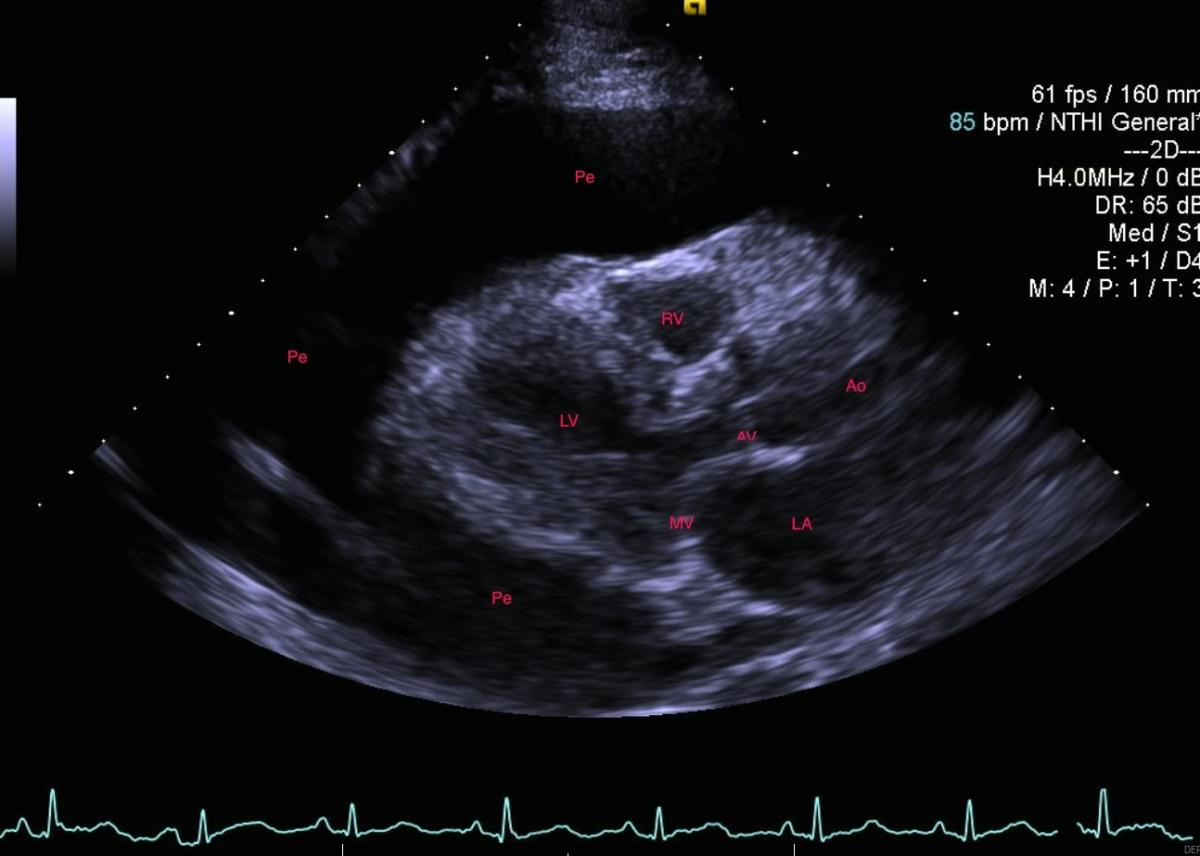

1.5 liters of serous, odorless fluid was removed and the echo appearance normalized, showing only trace pericardial fluid and a well-preserved ejection fraction. However, within four weeks the effusion re-accumulated as shown in the CXR (Fig.2) and echo showed early tamponade.

Cardiothoracic surgery was contacted for a pericardial window and biopsy. A repeat contrast enhanced chest CT scan suggested an 18 x 16 mm peripherally enhancing intrapericardial mass, with central low attenuation between the main pulmonary artery and the left atrial appendage. The pericardial effusion was massive, the pericardium was mildly thickened, and a right apical 3 mm pulmonary nodule was evident (Fig. 3).